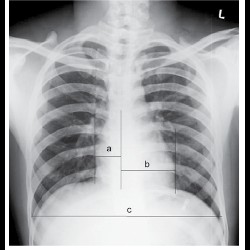

Role of Radiography in Congenital Heart Diseases

Role of Radiography in Congenital Heart Diseases

Role of Radiography in Congenital Heart Diseases

Role of Radiography in Congenital Heart Diseases